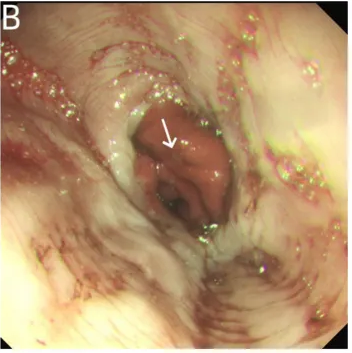

内镜下检查见气管及支气管黏膜明显充血。气管远端及右主支气管管壁覆盖少量白色物质。

床旁行胃镜检查贲门处有一大小约1 × 2.5 mm的浅溃疡,胃及十二指肠未见穿孔、溃疡及占位性病变。胃及十二指肠内可见少量气体。